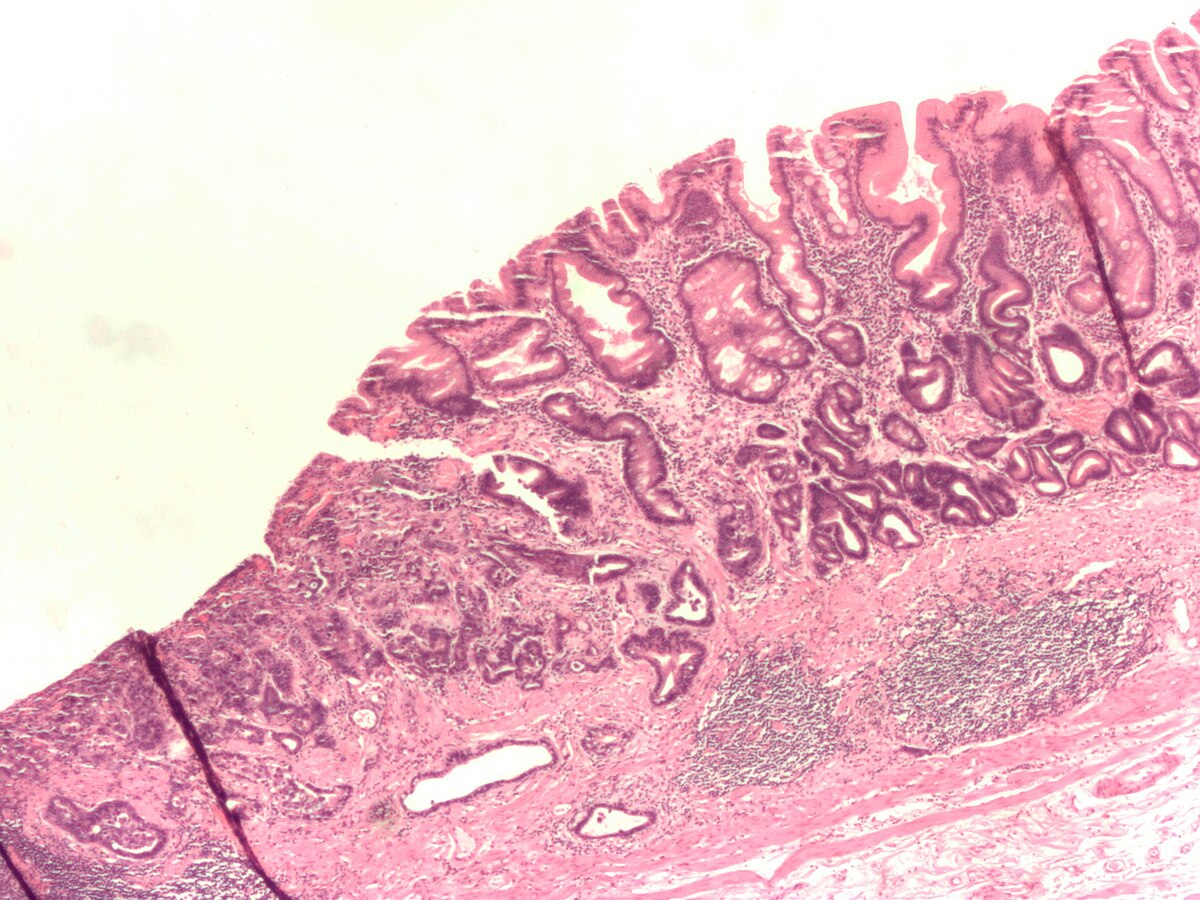

장상피화생, 즉 intestinal metaplasia는 위장관 질환의 중요한 병리학적 변화 중 하나로, 위 점막의 상피세포가 장 상피세포로 대체되는 현상을 일컫습니다. 이 변화는 종종 만성 위염이나 헬리코박터 파일로리 감염과 관련이 있으며, 이러한 병변이 암으로 발전할 가능성을 내포하고 있습니다. 이 글에서는 장상피화생이 암으로 변하는 과정과 그 기간, 그리고 위험 요인들에 대해 자세히 탐구해 보도록 하겠습니다.

장상피화생은 위 점막에서 발생하는 비정상적인 세포 변화로, 일반적으로 위점막이 장의 특수한 상피세포로 바뀌는过程입니다. 이는 다양한 원인에 의해 유발될 수 있으며, 위염, 흡연, 영양결핍, 그리고 유전적 요인 등이 포함됩니다. 장상피화생의 발생은 위암 발생 위험을 증가시키는 주요 원인이라고 알려져 있습니다.

장상피화생을 간단히 설명하자면, 정상적인 위점막 세포가 장관의 세포로 변형되어 특정한 환경에 적응하는 과정으로 볼 수 있습니다. 이러한 변화는 종종 위에서의 만성적인 자극에 대한 반응으로, 예를 들어, 헬리코박터 파일로리 감염에 의해 지속적인 염증이 발생할 경우 나타날 수 있습니다. 장상피화생이 진행됨에 따라 해당 조직의 세포가 비정상적으로 증식하게 되고, 이로 인해 암으로의 발전 가능성이 높아질 수 있습니다.